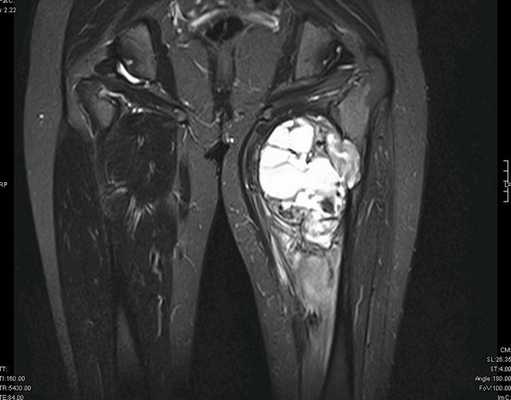

Рисунок №2. Саркома мягких тканей верхней трети левого бедра